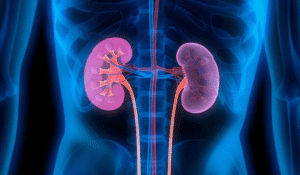

Bilinen en eski böbrek taşı ameliyatı da MÖ 400 yılında yapılmış.

1022 de Alman İmparatoru 2. Henri’ye, Monte Cassino manastırından alınan bir rahip tarafıdan böbrek taşı ameliyatı yapılmış. İmparator, böbreğinin 2 sene sonra tekrar taş yapması sonucu ölmüş.

1520’ye kadar uygulanan cerrahi yöntemlerde bir farklılık olmamış. Sonrasında da böbrek taşı amaliyatlarında yüksek ölüm oranı bilinen bir risk olarak kalmış.

1953’de ilk ultrasonik böbrek taşı kırma işlemi gerçekleştirilmiş. Ses üreten probe aşırı ısındığından etrafındaki dokuyu yakıyormuş.

İlk vücut dışından gönderilen şok dalgaları ile böbrek taşı kırma işlemi 1980’de Münih Üniversitesi Hastanesinde başarılmış.